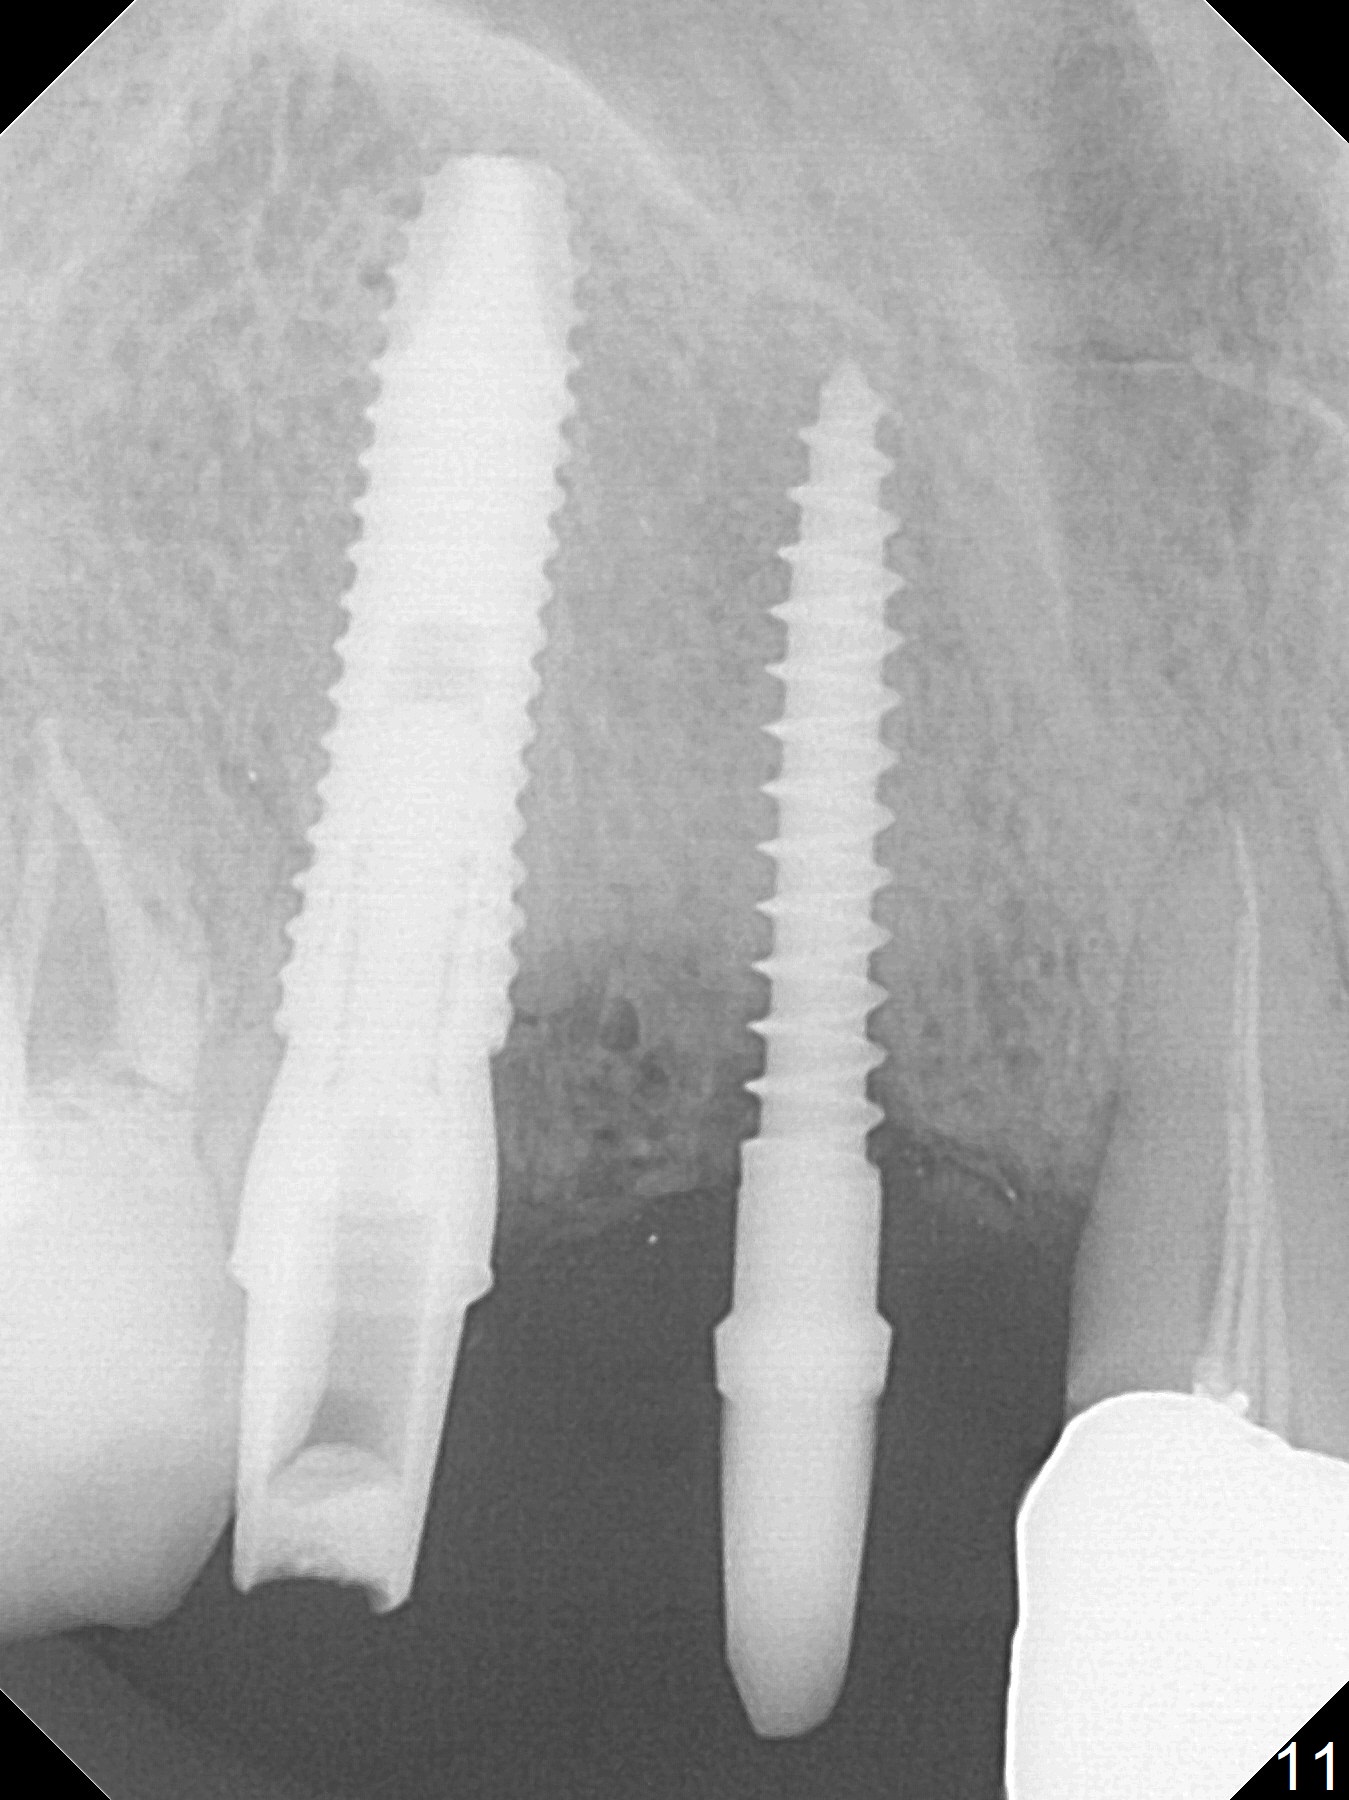

Since the ridge at #7 is ~ 4 mm, a 2.5x14 mm 1-piece implant is placed (Fig.8) after 1.2 mm (Fig.7), and 1.5 mm drills at 12 mm and 2 mm drill at 8 mm. Later the implant is placed deeper (Fig.10). There is no bone loss 7 or 12 months postop, respectively (Fig.11,12). After Diode gingivectomy, there is papillary formation (Fig.13). No provisional is provided after impression (with the abutment torqued at #6) for oral hygiene. With access holes at #6 and 7, crowns are bonded with minimal residual cement (Fig.14 <, which is removed later). There is no hard (Fig.15,16) or soft (Fig.17 *) atrophy 26 months postop, i.e., 13 months post cementation, due to the presence of socket shield (Fig.15 <, as compared to Fig.1). In fact the tooth #8 has mobility and fremitus (short root/poor crown/root ratio, Fig.16); occlusal adjustment is done 13 months post cementation. The crown is dislodged 2 years 1 month post cementation; a prefabricated post is being tried in (Fig.18). There is no atrophy, bone loss or infection at #6 (with socket sheath (*)) or 7 two years 5 months post cementation (Fig.20-27).